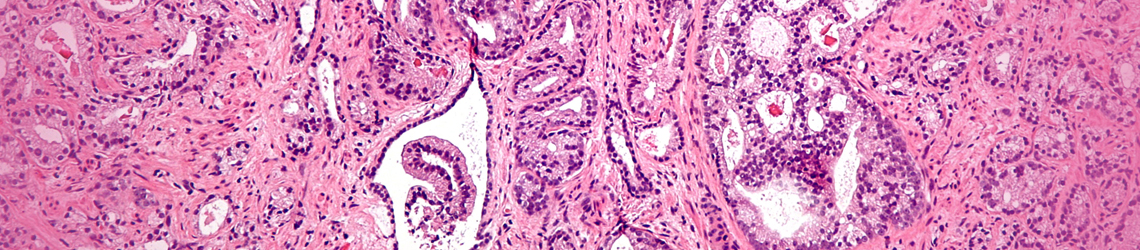

Prostate Adenoma

The prostate is a gland with a fibro muscular structure that surrounds the base of the bladder and is a part of the reproductive male system. With age, the prostate tends to enlarge; the medical term for this is benign prostatic hyperplasia. The growth of the different structures of the prostate determines the type of prostate adenoma. This is one of the most common benign tumors of men over 60 years old. Due to its localization around the urethra, once the prostate enlarges it can cause problems with urination.